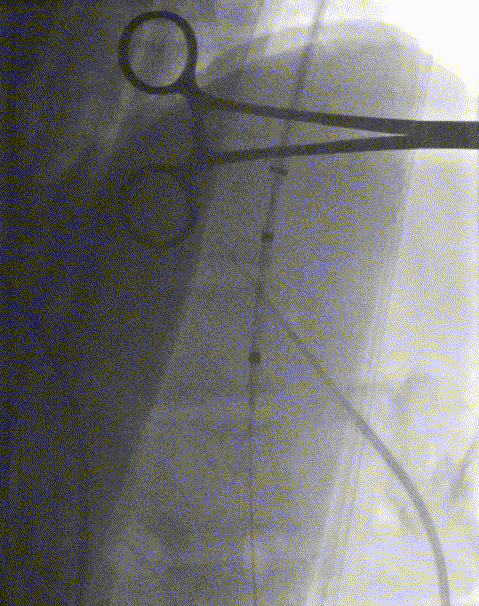

8. 置入8*50mm覆膜支架建立门静脉下腔静脉分流道。造影提示:分流效果满意。

患者进食正常,无腹痛。无肝性脑病。一月后体重增加10Kg。门静脉CTV:分流支架通畅。

该患者TEPS手术效果良好,患者腹痛消失,进食正常,无肝性脑病。评估出血风险后仍需抗凝治疗,提高支架远期通畅率。